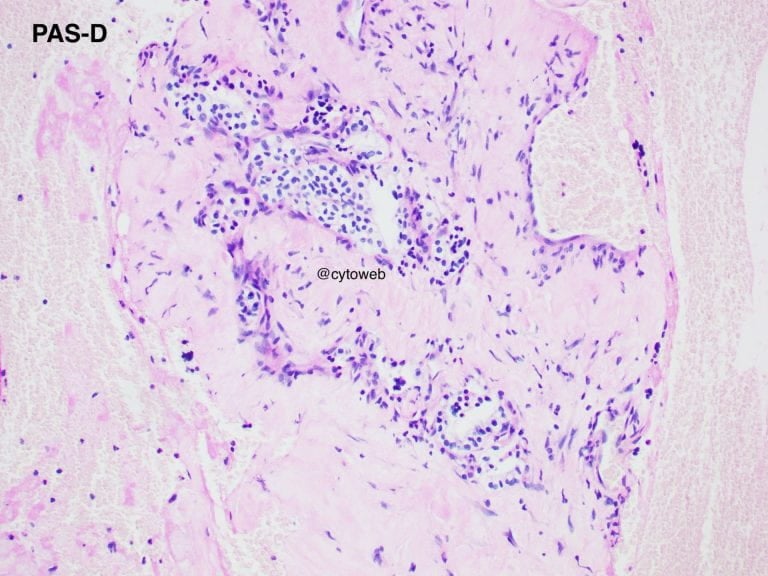

Clinical history: A 50-year-old female was found to have an incidental solitary multi-septated cyst in the pancreatic neck. There was enhancement of the septa of the cyst on CT imaging. Endoscopic ultrasound showed an echogenic central area. The cyst does not communicate with the pancreatic ductal system. Fine needle aspiration of the lesion was performed and 1ml of clear watery fluid was aspirated.